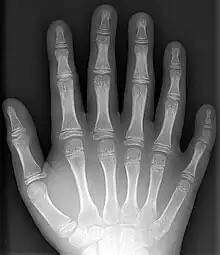

Polydaktyli er en misdannelse som indebærer, at man har flere end fem fingre på hver hånd eller flere end 5 tæer på hver fod. Begrebet stammer fra græsk, poly, mange og daktylos, finger. Det er arveligt, men optræder ofte uregelmæssigt, eftersom arveanlægget ikke altid manifesterer sig. Selvom tilstanden ikke er farlig, får de fleste mennesker i Vesten fjernet ekstra udvækster kirurgisk.

En ekstra finger vil kun sjældent være en komplet og velfungerende finger; normalt består den blot af muskelvæv og til tider også et stykke knogle uden forbindelse med de øvrige knogler. Normalt er den ekstra finger en lillefinger på siden af hånden, kun sjældent optræder den på tommelsiden af hånden, og i meget sjældne tilfælde findes den mellem de andre fingre.

Polydactyli kan optræde af sig selv, eller oftest, som et træk ved et syndrom af et medfødt afvigelse. Når det optræder af sig selv, er det associeret med dominerende mutationer i enkelte gener. Forholdet har en hyppighed på 2 for hver 1000 fødte barn[1], selvom hyppigheden er højere for enkelte grupper, et eksempel er amishfolket i USA grundet startpopulation.